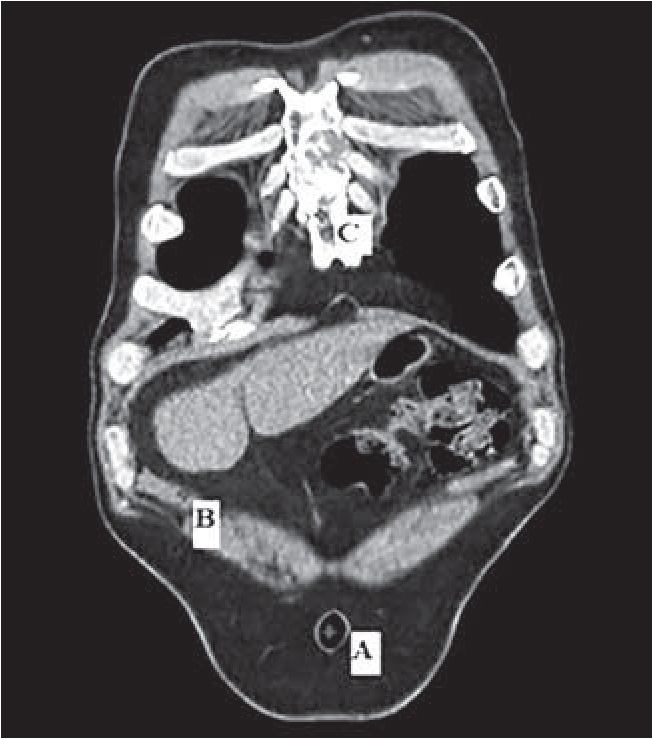

При анализе данных СКТ (для включения в исследование) оценивали состояние внепеченочных желчных путей (наличие либо отсутствие желчного пузыря, визуализация конкрементов во внепеченочных желчных путях) и сопутствующие заболевания органов брюшной полости, изменяющие анатомическое строение желчного пузыря. В последующем во фронтальной плоскости визуализировали центр пупка (точка А), дно желчного пузыря (точка В) и верхушку мечевидного отростка грудины (точка С) (рис. 2).

Рис. 2. Визуализация вершины мечевидного отростка грудины и пупка: А – пупок; В – проекция дна желчного пузыря на кожу; С – вершина мечевидного отростка

Точка В – проекция дна желчного пузыря на переднюю брюшную стенку (ПБС). Для её определения визуализировали в режиме многоплоскостных реконструкций наиболее близкую к ПБС часть желчного пузыря и фиксировали её с помощью измерительных инструментов компьютерной программы (рис. 3). Точка В1 соответствует проекции шейки желчного пузыря на ПБС, её определяли аналогичным образом.